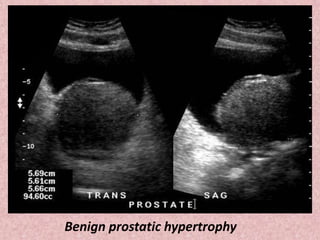

Benign prostatic hypertrophy

Transverse image of the prostate showing a

hypertrophied transition zone (yellow arrows)

and a compressed peripheral zone (blue arrows).

Benign prostatic hypertrophy.